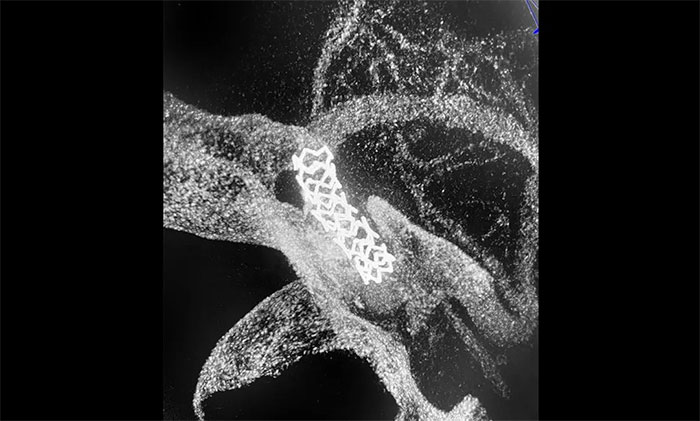

隨后,微導(dǎo)絲超選至左側(cè)大腦中動(dòng)脈M1段遠(yuǎn)端,并以多枚球囊擴(kuò)張殘余重度狹窄處,造影提示狹窄較前明顯改善,遠(yuǎn)端血流改善明顯。最后順利放入支架,造影提示支架貼壁良好,支架內(nèi)血流通暢,遠(yuǎn)端血流良好,手術(shù)順利完成。